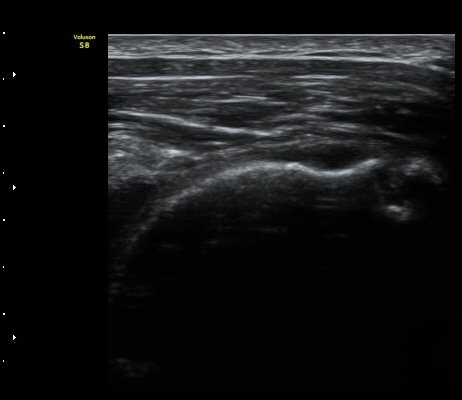

±Ø»ó°ÇȾ´Ü¸é°Ë»ç¿¡¼­ ±Ø»ó°ÇÀÇ ±¤¹üÀ§ÆÄ¿­ ¼Ò°ßÀ» º¸ÀÓ(»çÁø 4)

°ß°©ÇÏ±Ù°Ç Á¾´Ü¸é°Ë»ç¿Í Ⱦ´Ü¸é°Ë»ç¿¡¼­ °ß°©ÇϱٰÇÀÇ ÀüÃþÆÄ¿­ ¼Ò°ßÀ» º¸ÀÓ(»çÁø 5, 6)